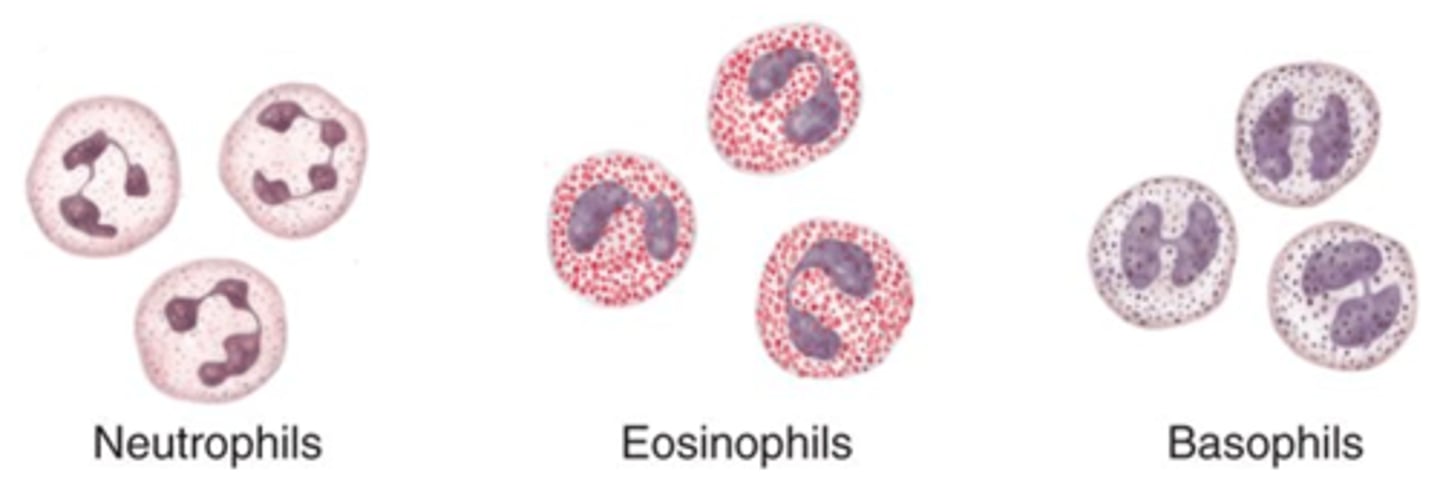

Granular leukocytes

Neutrophils, eosinophils, basophils

PHILLED (filled) with granules (enzymes)

Neutrophils

Structure: Nuclei has three or more lobes, granules stain light pink

Function: The most common WBC; fights bacterial infections by engulfing bacteria by phagocytosis

Where does the name neutrophils come from?

Their granules do not stain with acid OR basic dye -- they are neutral

Other name for neutrophils

Polymorphonuclear leukocytes (bc they have many lobes)

Eosiniphils

Structure: Nuclei has two lobes, granules stain bright red

Function: A WBC that digests and destroys parasitic worms, they also play a role in allergy and immune response

Where does the name eosinophils come from?

Their granules stain bright pink/red with acidic dye called eosin

Basophils

Structure: Nuclei is U or S shaped but is obstructed by HUGE blue granules

Function: A WBC that produces histamine --> causing inflammation during an immune response

Where does the name basophils come from?

Their granules stain blue with hematoxylin dye